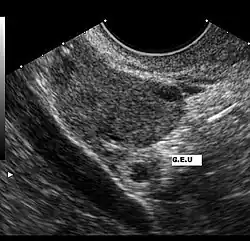

Grossesse extra-utérine (Petit cercle blanc)

L'échographie par sonde abdominale permet de visualiser une masse hétérogène latéro-utérine, constitué par le sac gestationnel en dehors de la cavité utérine. L'utérus est vide mais ses parois épaissies. Un épanchement au niveau du cul-de sac de Douglas peut être mis en évidence. Cet examen a une très bonne sensibilité pour le diagnostic mais une spécificité moins importante[8].

Des β-HCG supérieurs à 4000 UI/l sans visualisation du sac ovulaire intra-utérin signent pratiquement la grossesse extra-utérine.

L'examen échographique peut être complété par l'utilisation d'une sonde endovaginale, permettant de mieux visualiser trompes, ovaires et contenu utérin et d'avoir une précision diagnostique plus importante[9].